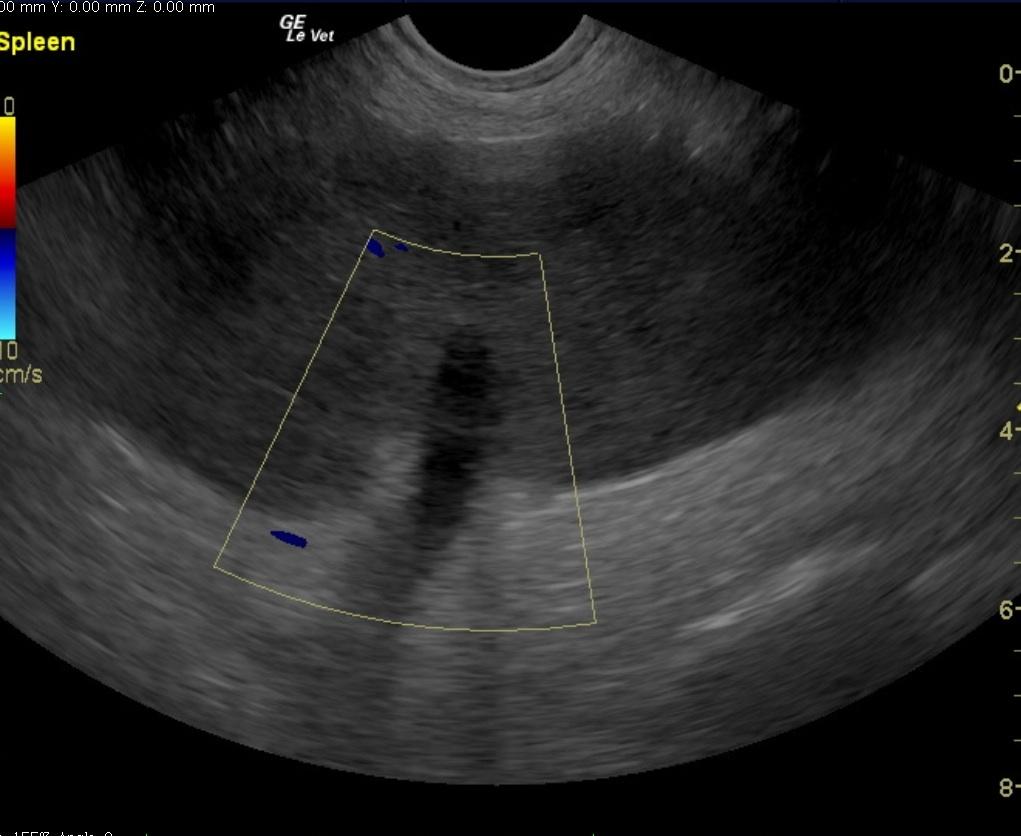

A 6-year-old intact male English Bulldog was presented for 2-3 days of intermittent vomiting and lethargy. Physical exam found the patient to be tachycardic with pale mucous membranes and a palpable mass in the abdomen. Serum biochemistry revealed elevated alkaline phosphatase, hypernatremia, and mild hypochloremia. On CBC, a decreased HCT in conjunction with a high MCV was noted, in addition to a neutrophilia, monocytosis and thrombocytopenia. No abnormalities were noted on thoracic radiographs. Abdominal radiographic findings revealed a loss of contrast in the cranial abdomen, with the possibility of a splenic mass. Radiographic Interpretation showed marked splenomegaly strongly suspected to be secondary to torsion, although accompanying infiltrative or neoplastic pathology could not be ruled out. The small volume of peritoneal effusion and inflammation was likely secondary to the splenic pathology. Thoracic radiographs showed mild microcardia and under perfused pulmonary vasculature in support of hypovolemia. Atypical intrathoracic fat distribution was considered to be incidental in this dog. This dog had multiple hemivertebrae.